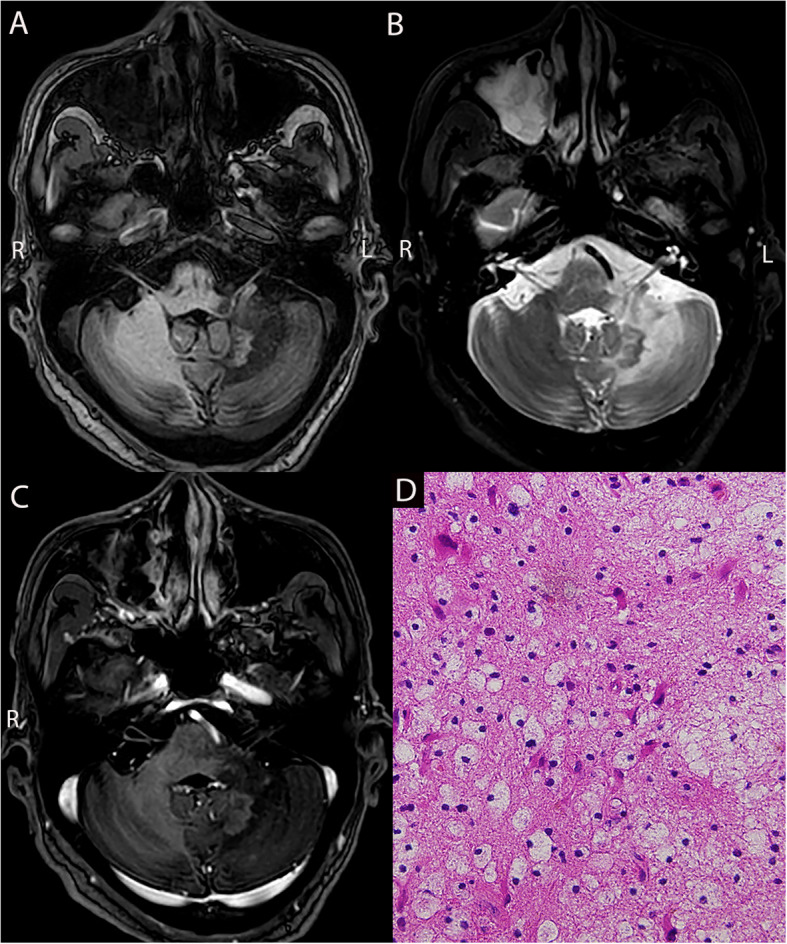

Methods: We retrospectively collected clinical data from 22 patients with LCL and analyzed their magnetic resonance imaging and pathological characteristics. Pathological diagnoses were made using stereotactic intracranial puncture biopsy.

Results: Between April 2003 and December 2023, 22 patients with LCL were admitted, including 18 males and 4 females aged 7-71 years. Bone marrow aspiration identified 14 cases of acute lymphoblastic leukemia (ALL), one of chronic lymphoblastic leukemia, six of acute myeloid leukemia (AML), and one of chronic myelomonocytic leukemia (CMML). Most patients presented with non-specific symptoms, including headache, nausea, vomiting, limb convulsions, and changes in mental status. A few patients had localized neurological deficits, such as limb weakness and blurred vision. Common systemic symptoms included fever, night sweats, and weight loss. The pathological diagnoses of the 22 patients were CNSL in 13 patients, CNS infections in five patients, and neurodegenerative diseases in four patients. Discrepancies were found between the clinical and pathological diagnoses in eight cases.